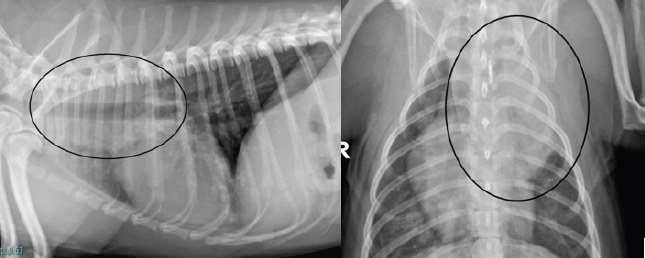

At the 2-week revisit, the owner reported the coughing had resolved. Radiographs of the chest were repeated and revealed marked improvement with the larger lung opacity on the left cranial lung field becoming significantly smaller. The dose of prednisolone was reduced to 1 mg/kg PO q 24 hours for 2 more weeks. Continued clinical improvement was reported by the owner and was documented in the thoracic radiographs at the 4-week revisit. Complete resolution of clinical signs and radiographical lesions was observed at week 10 (Fig. 6). The dose of prednisolone was tapered off over the following 8 weeks and then stopped. The dog is currently doing well with no signs of recurrence over 1 year after the initial presentation.

Fig. 6. Left lateral and dorsoventral thoracic radiographs 10 weeks following corticosteroid treatment.